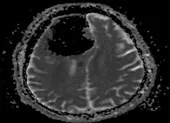

(PLO)- Tối 26-10, bệnh viện (BV) Đa khoa Xuyên Á (TP.HCM) cho biết nơi đây vừa phẫu thuật thành công khối u não mặt sau xương đá, một vị trí vô cùng nguy hiểm trong não cho bệnh nhân NTT (50 tuổi, ở tỉnh Tây Ninh).